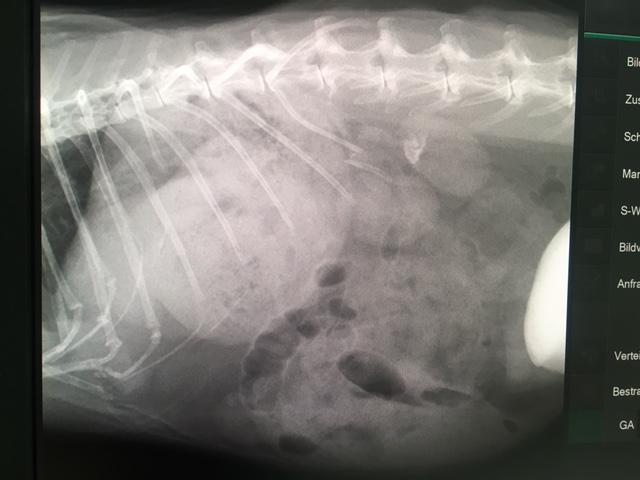

Bei meinem Tierarzt-Check stellte sich heraus, dass ich leider einige doch massive Baustellen aufweise. Meine Zähne sehen miserabel aus und mussten gleich in Narkose saniert und zwei davon gezogen werden. Meine Pflegestelle bemerkte außerdem, dass ich so kreideartige Flecken beim Pipi machen am Boden hinterlassen hab, was ein Indiz für Blasengrieß/-schlamm ist. Überhaupt wirke ich insgesamt oben bei der Wirbelsäule recht dünn und untenrum hab ich einen großen dicken Kugelbauch. Daher wurde auch sogleich ein Röntgen gemacht, wo man das restliche Ausmaß meiner Beschwerden sah. Ich hab extremen Blasengrieß, eine vergrößerte/verkalkte Leber und eine gebrochene Rippe. Die Blase wurde sogleich von dem kaninchenerfahrenen Tierarzt ausgedrückt, um meine Schmerzen zu lindern und ich bekomme (u.a. auch homöopathische) Medikamente und werde von meiner neuen Gnadenhofmama nun richtig ernährt. Wichtig ist bei Blasengrieß kein Trockenfutter und viel frische kalziumarme Ernährung und ich futtere brav und mit voller Begeisterung meine neuen gesunden Leckerlies. Da ich regelmäßige tierärztliche Behandlungen benötige und meine Blase und Leber/Niere ja wieder funktionstüchtiger werden sollen, darf ich trotz Platzmangel noch auf einem Gnadenhofplatz der Helpline bleiben. Hier wohne ich mit einem netten älteren Mädel in einem schönen Gehege und hoffe, dass ich aufgrund der guten Betreuung mein neu gewonnenes Leben noch lange genießen kann. (März 2017)